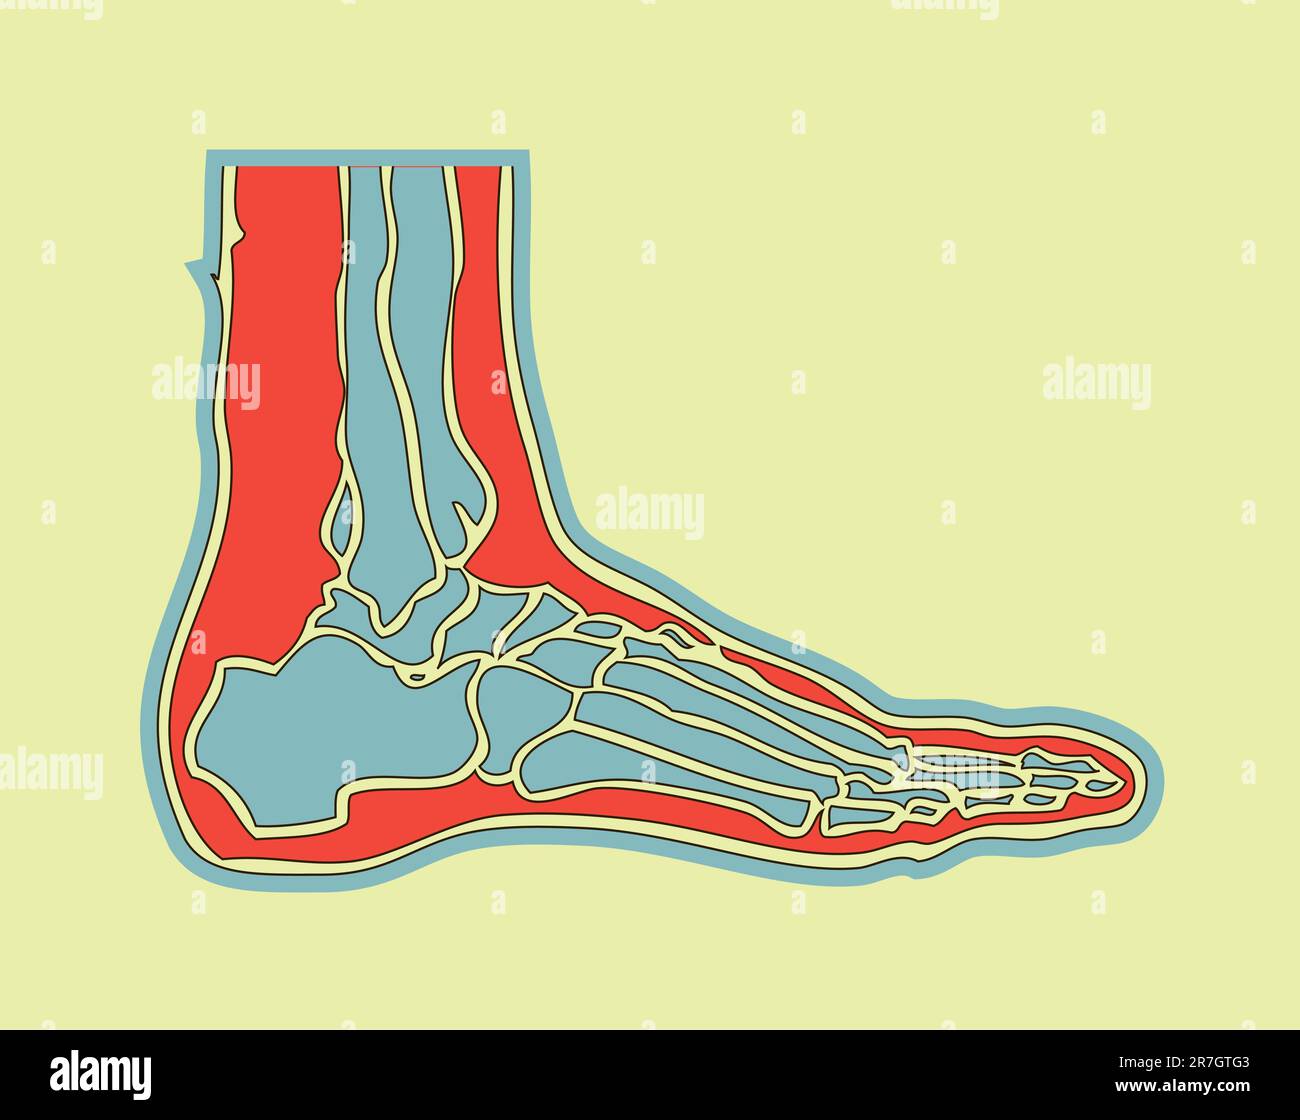

RF2R3WKY1–Illustration médicale des principales parties des os du pied en vue latérale, avec annotations.

RF2HJXCXK–Anatomie du pied.OS et fascia Plantar.Illustration vectorielle réaliste. Vue de dessous et vue latérale